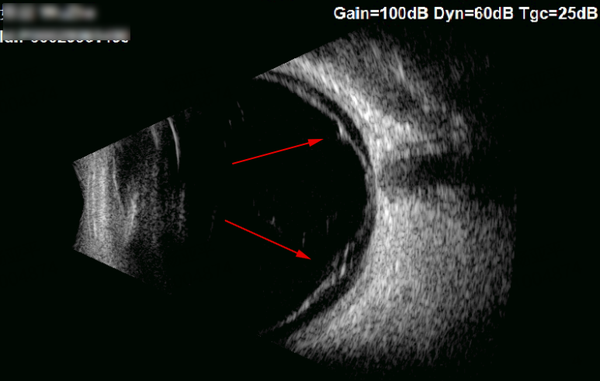

“孩子的眼轴长度已经超过26毫米,而同龄儿童正常眼轴长度约为23-24毫米。”眼底病专家、爱尔眼科鄂豫区副总院长李玉军介绍,

“这个孩子的情况已经属于病理性的高度近视,视网膜就像一个被过度拉伸的气球,变得薄而脆弱,不当的外力极易发生裂孔和脱离。”